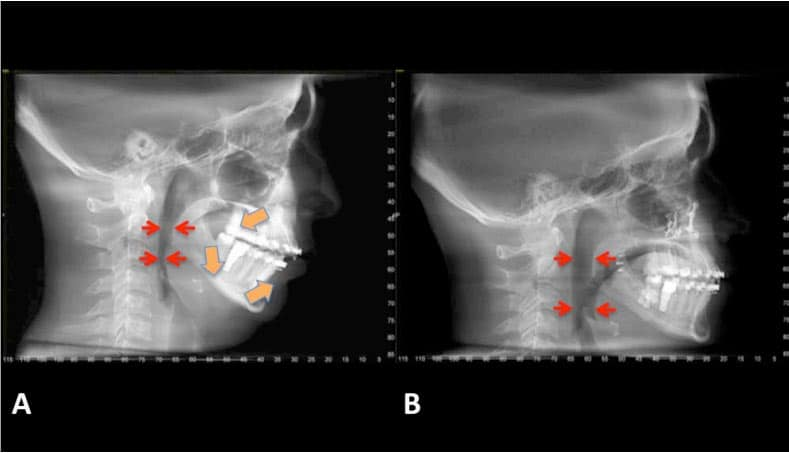

my maxilla is recessed and im getting lefort one in around 6 months

looking to find out how much this will help me overall and what changes I might see

also, will it get rid of my smile lines?